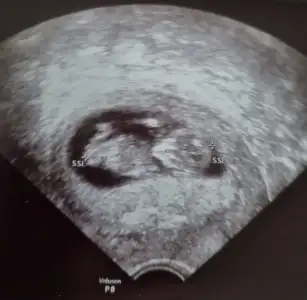

Ben size yazmıştım kız dedim diğer konudaBana ısrarla bakmadınız 12 hafta karından![]()

Ben size yazmıştım kız dedim diğer konuda